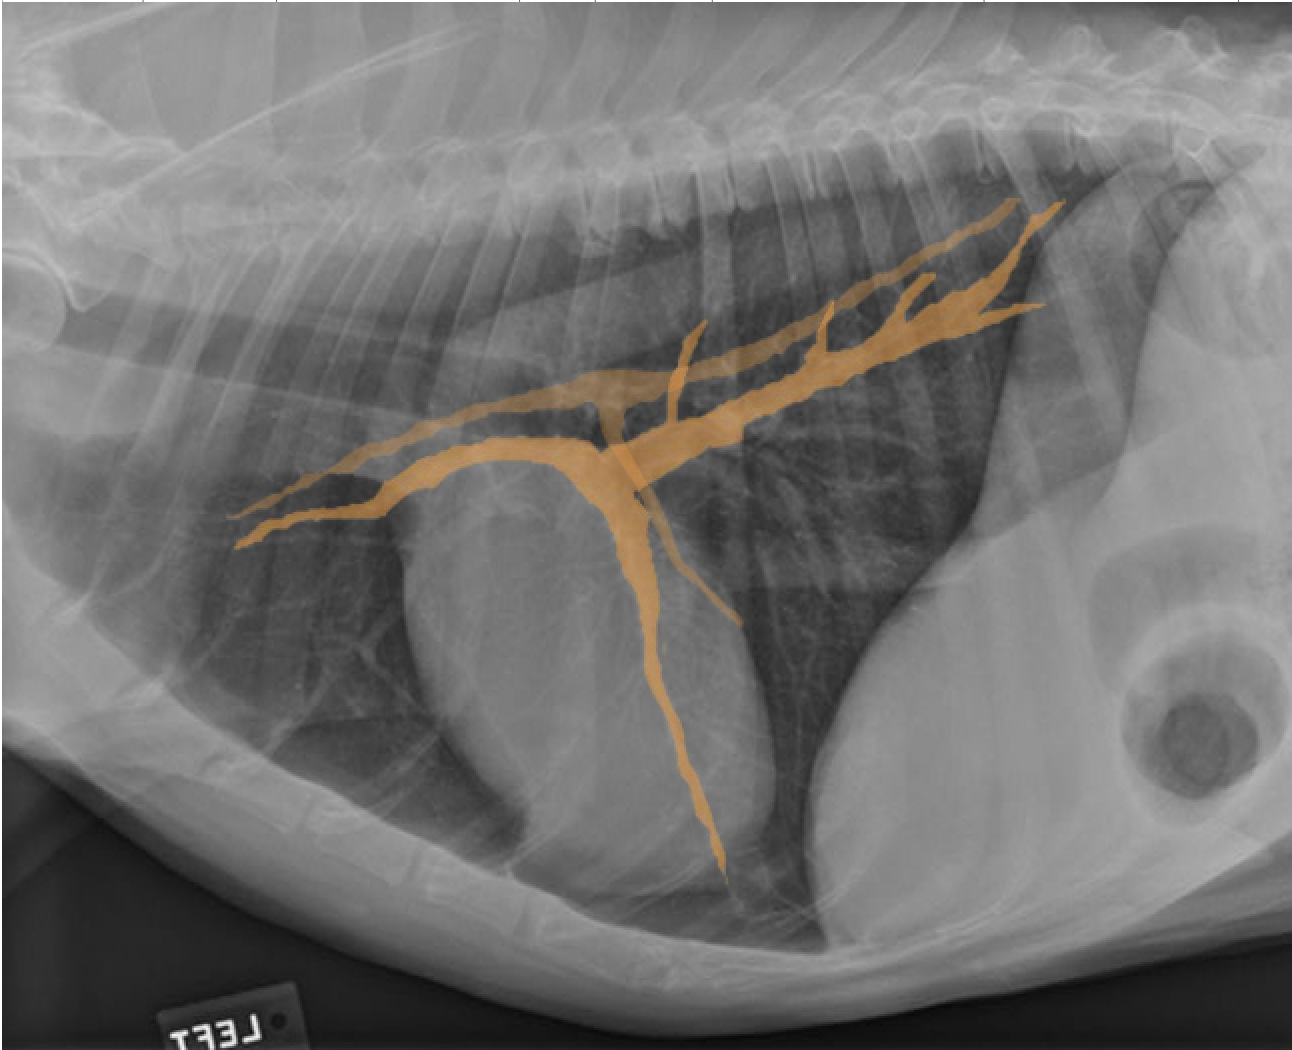

identity the structures on the thorax radiograph left lateral view

identify the right cranial pulmonary vein

identify the pulmonary arteries